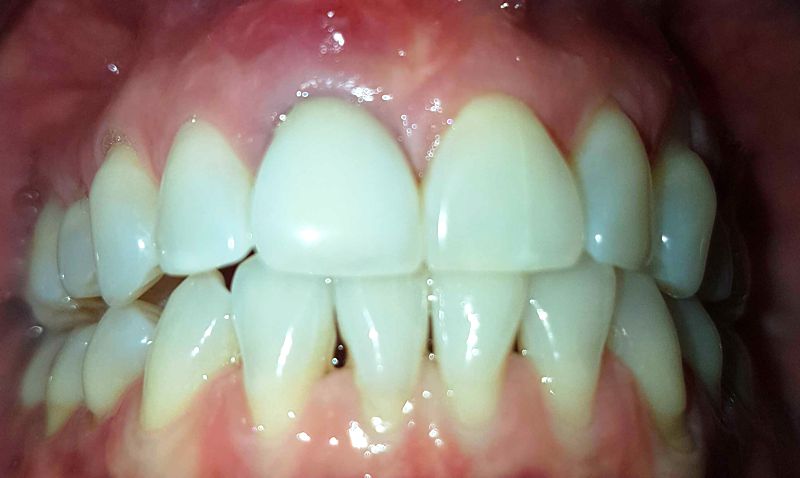

Zuerst müssen wir uns vergegenwärtigen wie gesunde Zähne aussehen:

Das Zahnfleisch ist homogen hell-pink, die Zähne alle weiss.